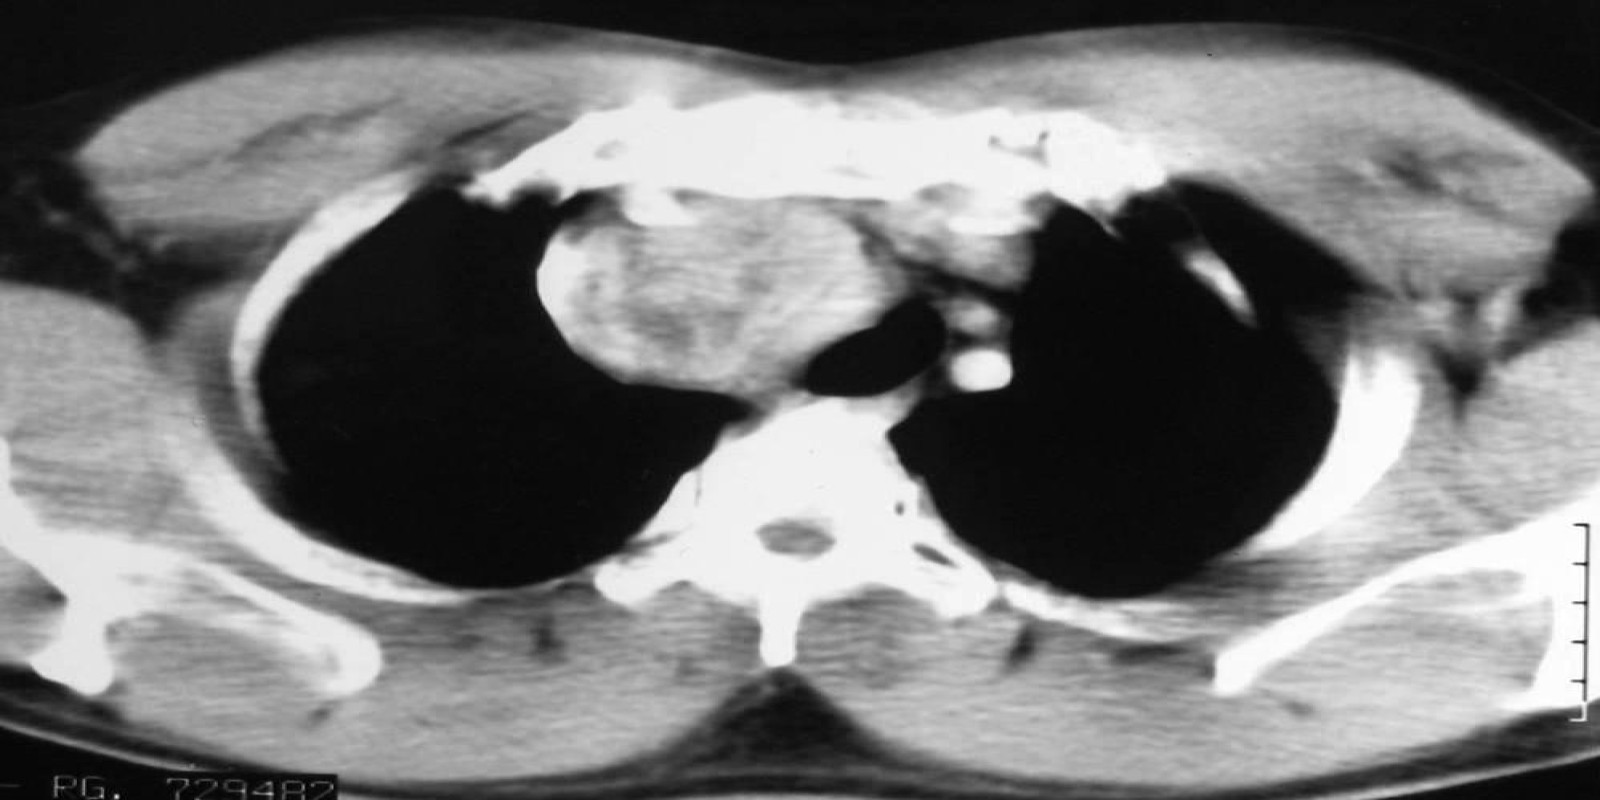

Tireóide ectópica mediastinal

Ectopic Mediastinal Thyroid